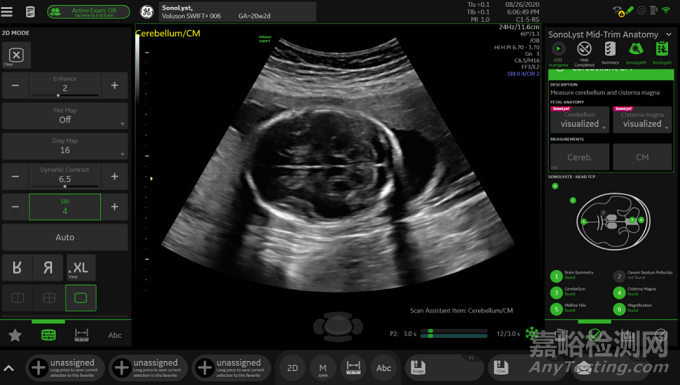

圖2 經(jīng)小腦平面的智能產(chǎn)篩功能輸出圖像

圖2為智能產(chǎn)篩功能輸出結果的一個示例。凍結后,“識別”功能對圖像進行了分析,識別出了經(jīng)小腦平面(TCP)。由于用戶在設置智能導航時將TCP切面放進了掃查項目,因此智能產(chǎn)篩功能“識別”到了“Cerebellum/CM(小腦/CM)”掃查項目,該掃查項目頂部會出現(xiàn)粉紅色“SonoLyst”標志。當用戶按下“質控”圖標,“質控”功能會根據(jù)特征結構(包括大腦的對稱性、小腦等)的識別結果,填寫各項掃查標準的評估結果:“found(發(fā)現(xiàn))”或“not found(未發(fā)現(xiàn))”。